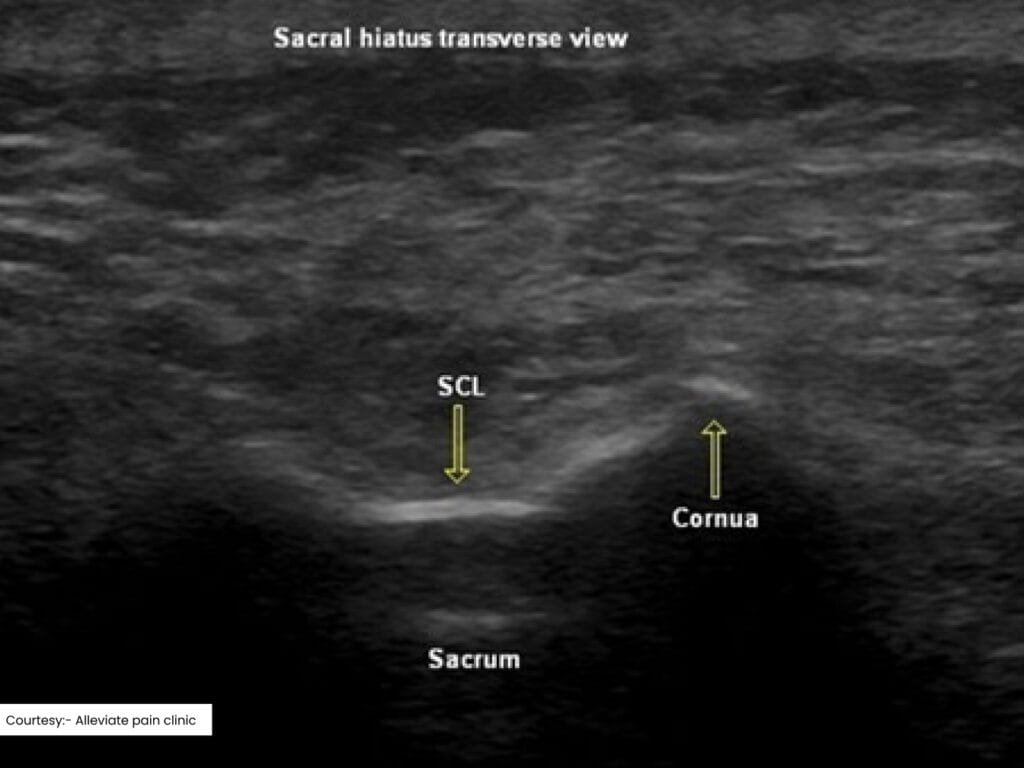

- Ultrasound: Offers real-time visualization of soft tissues and nerves without radiation exposure. It’s a viable option for patients for whom minimizing radiation is a priority.

Ultrasound guided caudal epidural injection